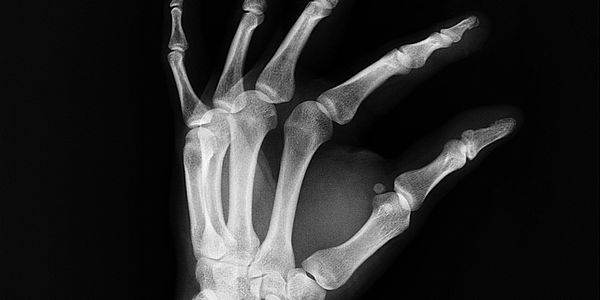

適合用來改善項目如五十肩、關節炎、退化性骨關節疾病、坐骨神經痛、下背痛、頸脊椎退化壓迫、脊椎側彎、肩頸痠痛、落枕、脊椎及關節手術後復健、網球肘、高爾夫球肘、肌腱炎、筋膜炎、筋膜痛症、扭傷挫傷、運動傷害、神經相關疾病復健、各種急慢性疼痛。